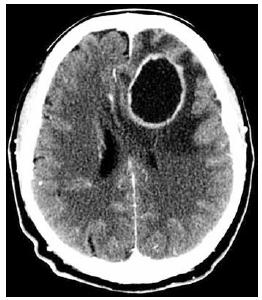

Homem de 43 anos de idade apresenta quadro de tosse produtiva e secreção nasal purulenta há 1 mês. Há 2 semanas evolui com febre, cefaleia, queda do estado geral, sonolência e alteração do comportamento. Ao exame físico: PA: 128 x 82 mmHg, FC: 115 bpm, FR: 22 ipm, SatO2: 95% e T: 38,5 ºC. A tomografia realizada é mostrada a seguir.

O tratamento inicial recomendado é